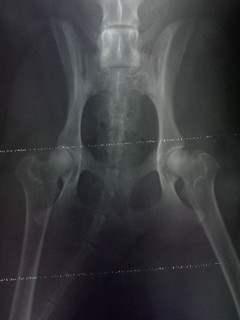

Ninja's Hips (Ventral Dorsal View)